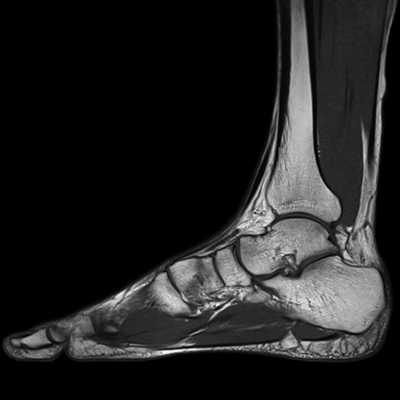

4. МРТ при переломе тела и отростков таранной кости:

• Если перелом в свое время не был замечен, пациенты могут быть направлены на МРТ уже по поводу хронических болей

Что показывает МРТ голеностопного сустава

МРТ – безвредное исследование с высокой степенью информативности. То, что показывает МРТ голеностопного сустава, помогает врачам в диагностике заболеваний, в наблюдении за развитием патологического процесса, результатами лечения. Особая роль принадлежит МР исследованию при подготовке к оперативному лечению.

МРТ не делается ургентно или при первом обращении больного за медицинской помощью. Сначала врач изучает жалобы, как появились и развивались симптомы заболевания, проводит осмотр, пальпацию, исследует объем движений в суставе и степень болезненности.

Первым методом, к которому прибегает врач, является рентген как самый недорогой и достаточно информативный метод визуализации. На снимках можно будет определить перелом, вывих, большие трещины, объемные образования в области сустава.

Вторым по частоте методом исследования идет УЗИ. При этом можно измерить толщину тканей – капсулы, хряща, сухожилия, определить ширину суставной щели, кисты, опухоли, увеличение количества внутрисуставной жидкости.

Но самым точным диагностическим методом является МРТ. При этом на снимках можно выявить изменения в структуре тканей менее 1 мм. Поэтому любая патология на МРТ будет видна намного раньше, чем при других методах исследования. А это большое преимущество в лечении, ведь чем раньше начать его, тем оно эффективнее. Иногда на ранней стадии можно обойтись без хирургического лечения. В случаях выявления опухолей шансы излечиться намного выше, при этом методы будут более щадящими, меньше объем оперативного вмешательства.